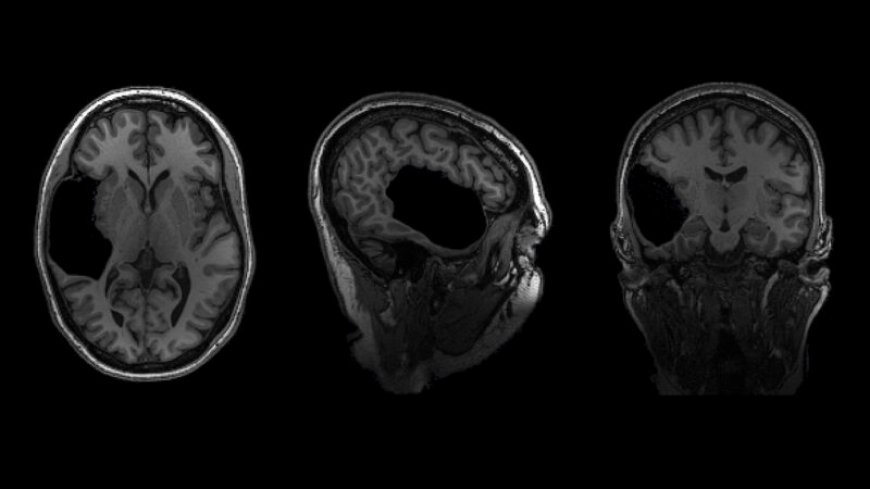

Looking at her brain scans is a different story. It’s as if someone has knocked over a bottle of ink. The darkness pools inside her skull near her left ear, a puddle of fuliginous black. Inside the splotch, there’s no white matter or gray matter, no blood vessels or tissue at all.

Elyse says you don’t have to be a neurosurgeon to spot what’s different about her brain: “There’s a big honking piece missing!”

Scientists can’t say exactly how it happened. It’s possible that sometime long ago, perhaps due to a stroke before or shortly after birth, a portion of Elyse’s brain died and then ultimately disappeared, leaving behind only liquid — brain tissue swapped for a fluid-filled void. Her sister has one too.

Elyse and her sister, Martha M., who are not using their full names to maintain their anonymity, look and act perfectly ordinary. But each lacks most of a temporal lobe, and each in a different hemisphere. Elyse is also missing part of her brain stem. The women are two of who knows how many people living their lives without brain structures generally thought to be crucial.